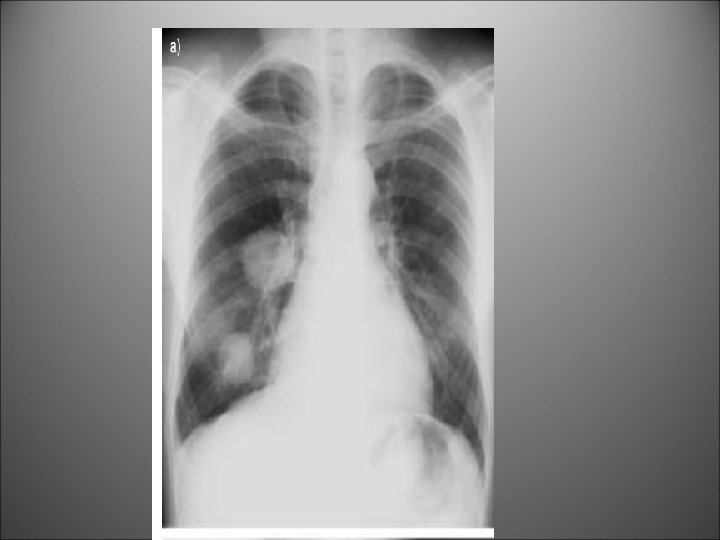

Hydatid cyst in lung. This patient had a single large cyst in the left

Hydatid cyst in lung. This patient had a single large cyst in the left lung.